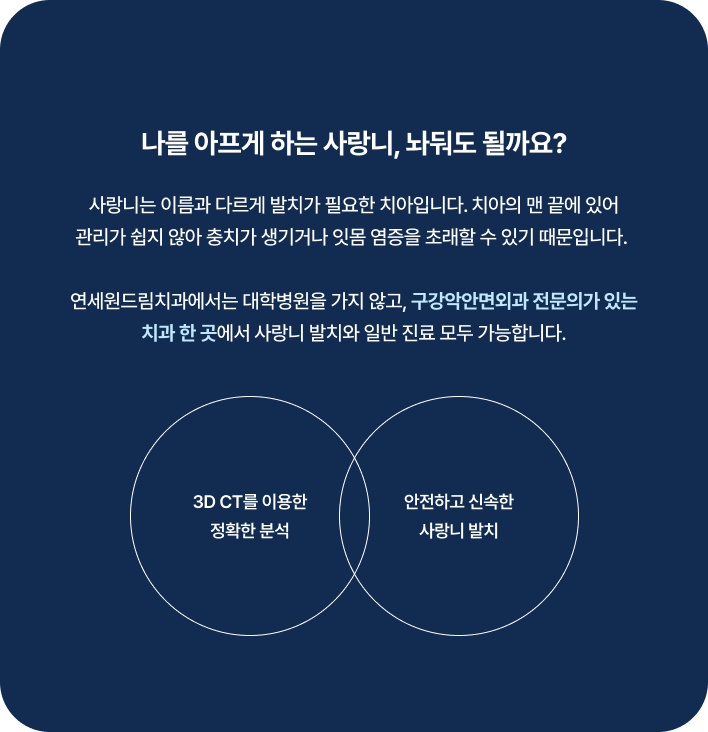

매복 사랑니 발치

수술 담당 구강악안면외과 전문의

고난도 수술 진료

임플란트와 사랑니 발치는 외과적 시술로 잇몸을 절개하는 외과적 시술은

짧으면 짧을 수록 시술 후 붓기와 통증이 최소화됩니다.

치과의사 경력 14년차 구강외과 전문의가 빠르고 안전하게, 아프지 않게 수술해 드립니다.

치과경력 14년차 구강외과 전문의

연세대학교 치과대학 구강외과 임상 조교수